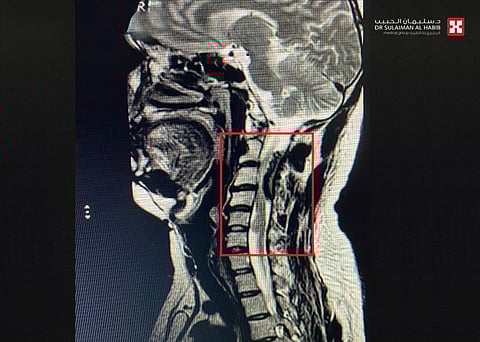

وقال د.هاني: إنه بعد إجراء الفحص السريري الأولي بالعيادة تبيّن تعرض المريض لآلام حادة في منطقة العنق، وضعف بقبضة اليدين، وتيبس بالساقين وعدم القدرة على المشي، موضحًا أنه تم على الفور إخضاعه لحزمة من الفحوصات الدقيقة المخبرية، بالإضافة إلى أشعة الرنين المغناطيسي الملون "M.R.I"، وقد أشارت النتائج إلى وجود ورم سحائي كبير تسبّب في حدوث ضغط هائل على الحبل الشوكي في المنطقة الواقعة بين الفقرة العنقية الثانية والسادسة، وكذلك اكتشاف ورم عصبي آخر ضاغط على العصب من الأمام بالفقرة الخامسة حتى السادسة؛ الأمر الذي يوضح أسباب الأعراض التي يشعر بها المريض، كما تم إجراء فحوصات على كامل الجسم للتأكد من عدم وجود أية أورام أخرى.